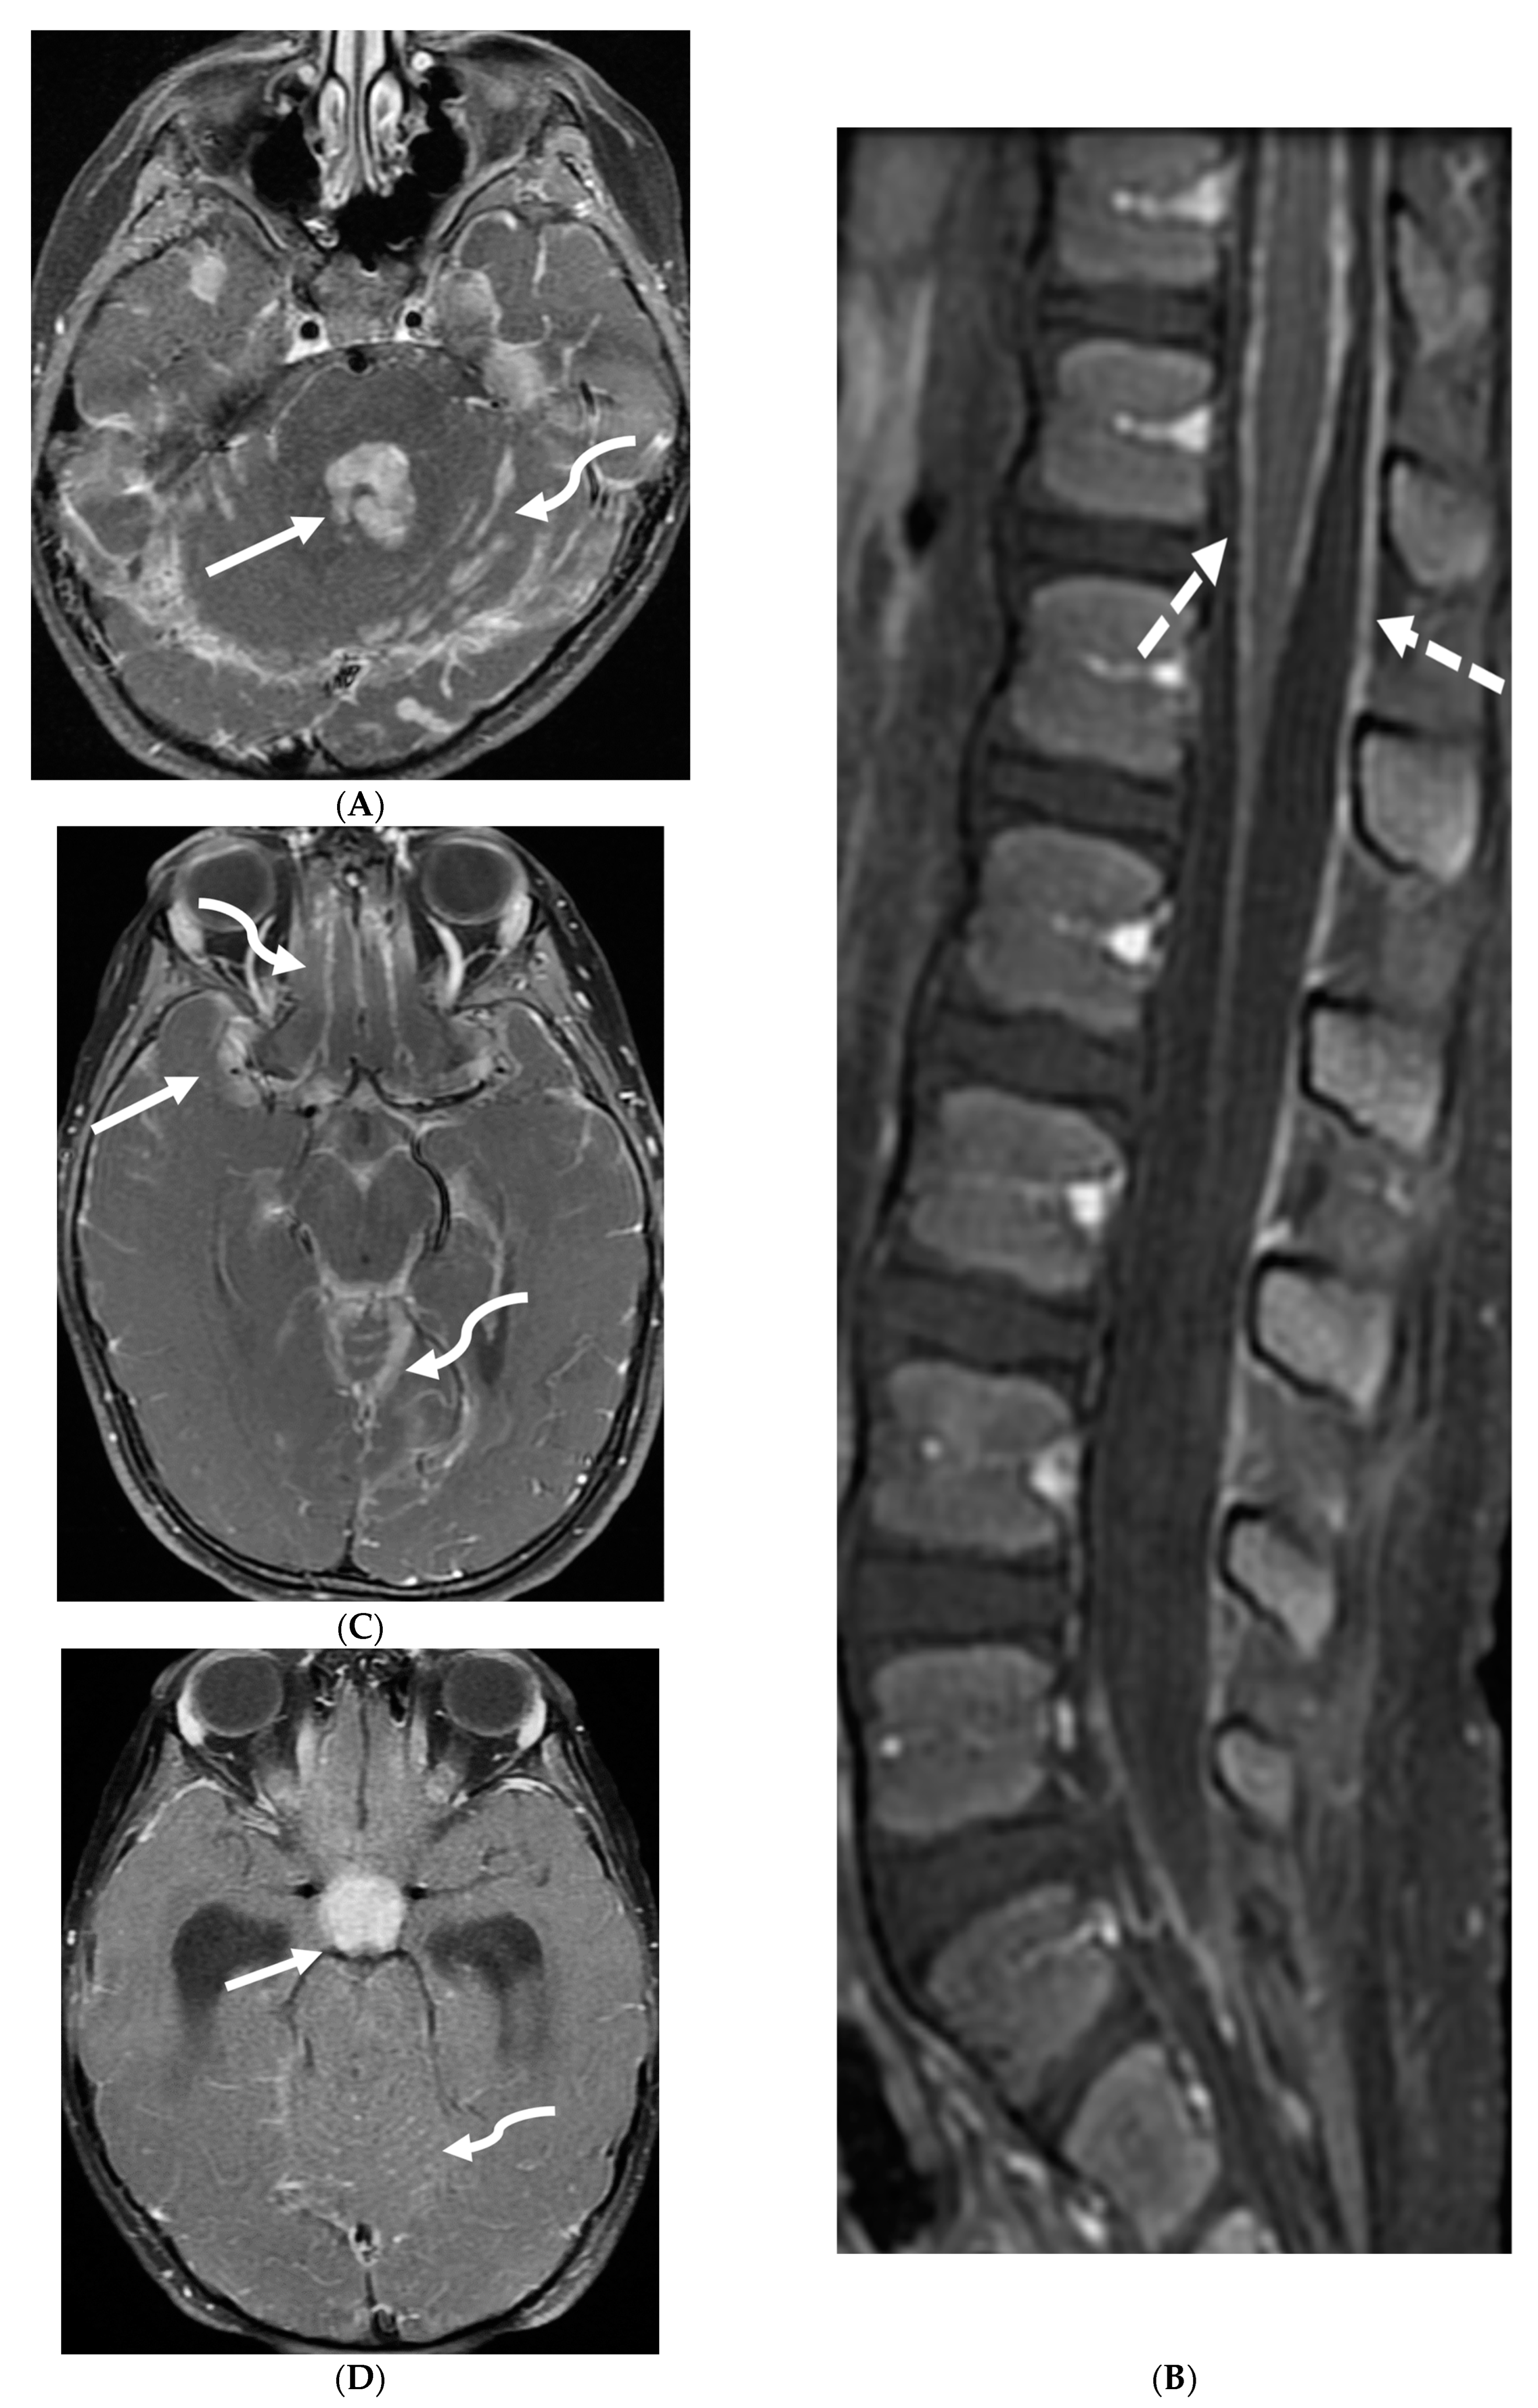

Fungal infections of the central nervous system (CNS) can be broadly categorized into two forms based on the causative organism’s size and pathogenesis. Yeast infections (e.g., Cryptococcus, Candida) are smaller and disseminate hematogenously, resulting in parenchymal granulomas, abscesses, and diffuse leptomeningitis. Mold infections (e.g., Aspergillus, Mucorales) are larger fungi that are restricted from entering the meningeal microcirculation, leading to more focal disease manifestations such as cerebritis, abscess formation, vasculitis, infarct, and mycotic aneurysm [99]. Candida is the most common fungal organism affecting children, typically in preterm and/or low birth weight neonates [100]. The routes of CNS invasion by fungal pathogens include hematogenous dissemination from a distant source (commonly lung), direct inoculation following trauma or neurosurgical procedures, and local extension from adjacent structures like the paranasal sinuses, orbit, or spine [101].

MRI findings in fungal meningitis include LME, which can be smooth or thick, nodular and irregular, and commonly involve the cortical sulci [102]. While a smooth, linear enhancement pattern is common in viral and bacterial meningitis, it can also be seen in immunocompetent patients with fungal meningitis [102]. Inflammatory exudates containing cell debris, fibrin, and hemorrhage can deposit in the subarachnoid space, leading to arachnoiditis. Protein accumulation in the subarachnoid space shortens T1 relaxation time and results in increased signal intensity on FLAIR sequences [102]. Meningeal adhesions can obstruct arachnoid granulations, leading to impaired cerebrospinal fluid (CSF) drainage and secondary hydrocephalus. Fungal brain abscesses typically demonstrate a central T1 hypointense and T2 hyperintense core, surrounded by a T1 iso-to-hyperintense and T2 hypointense enhancing peripheral rim (Figure 20) [103,104].

Figure 20.

Axial T2 (A), axial DWI (B), axial SWI (C) and axial T1 post contrast (D): 4-year-old girl with acute lymphoblastic leukemia, pancytopenia and fever. Treatment started one week before with asparaginase. There is prominently T2 hyperintensity and swelling of the gyri involving the medial aspect of the left parietal occipital cortex (arrow). Multiple small foci of T2 hypointensities are identified within the involved region with corresponding blooming on the susceptibility indicating hemorrhage (curved arrow) and peripheral rim of true restricted diffusion (dashed arrow). Postcontrast images show pachymeningeal and LME in the involved region (open arrows). Features are concerning for fungal infection. Pathology revealed Rhizomucor pusillis (thermophilic fungus).